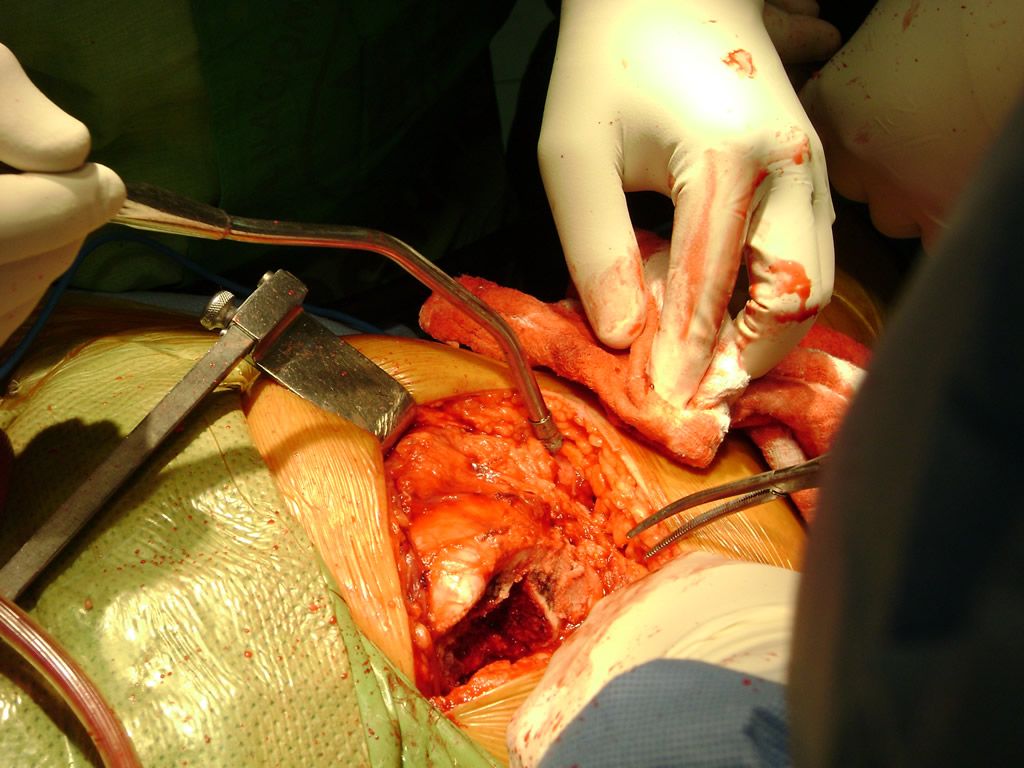

Calcaneo - Perone y Tibia

Aunque cada uno de estos huesos puede fracturarse por separado, normalmente la rotura es una lesión que se produce de forma conjunta

Debido a la fina cobertura de piel que recubre la tibia y el peroné, las fracturas generalmente son abiertas, es decir, el hueso roto rasga la piel, atravesándola. Las fracturas de tibia y peroné generalmente se producen por un fuerte impacto o torsión.